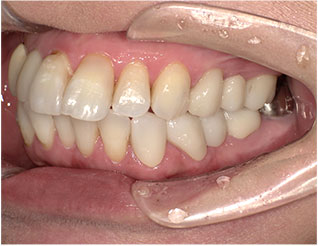

- ブリッジ 症例写真 B-0112FZC3本 女性モニターの方です。

Before

After詳細はコチラ

フルジルコニアによるブリッジ治療の症例

- No. B-0112

施術 FZC3本 - コメント

この方は奥歯が虫歯で根だけになってしまっていました。 この歯は抜歯し、ブリッジで治しました。 当院では強度が高く色がきれいなジルコニアブリッジで治しております。 歯型を取らずに、口腔内スキャナーでジルコニアブリッジを作成しますので、精度の高いブリッジを入れることが可能です。 治療回数は3回でした。